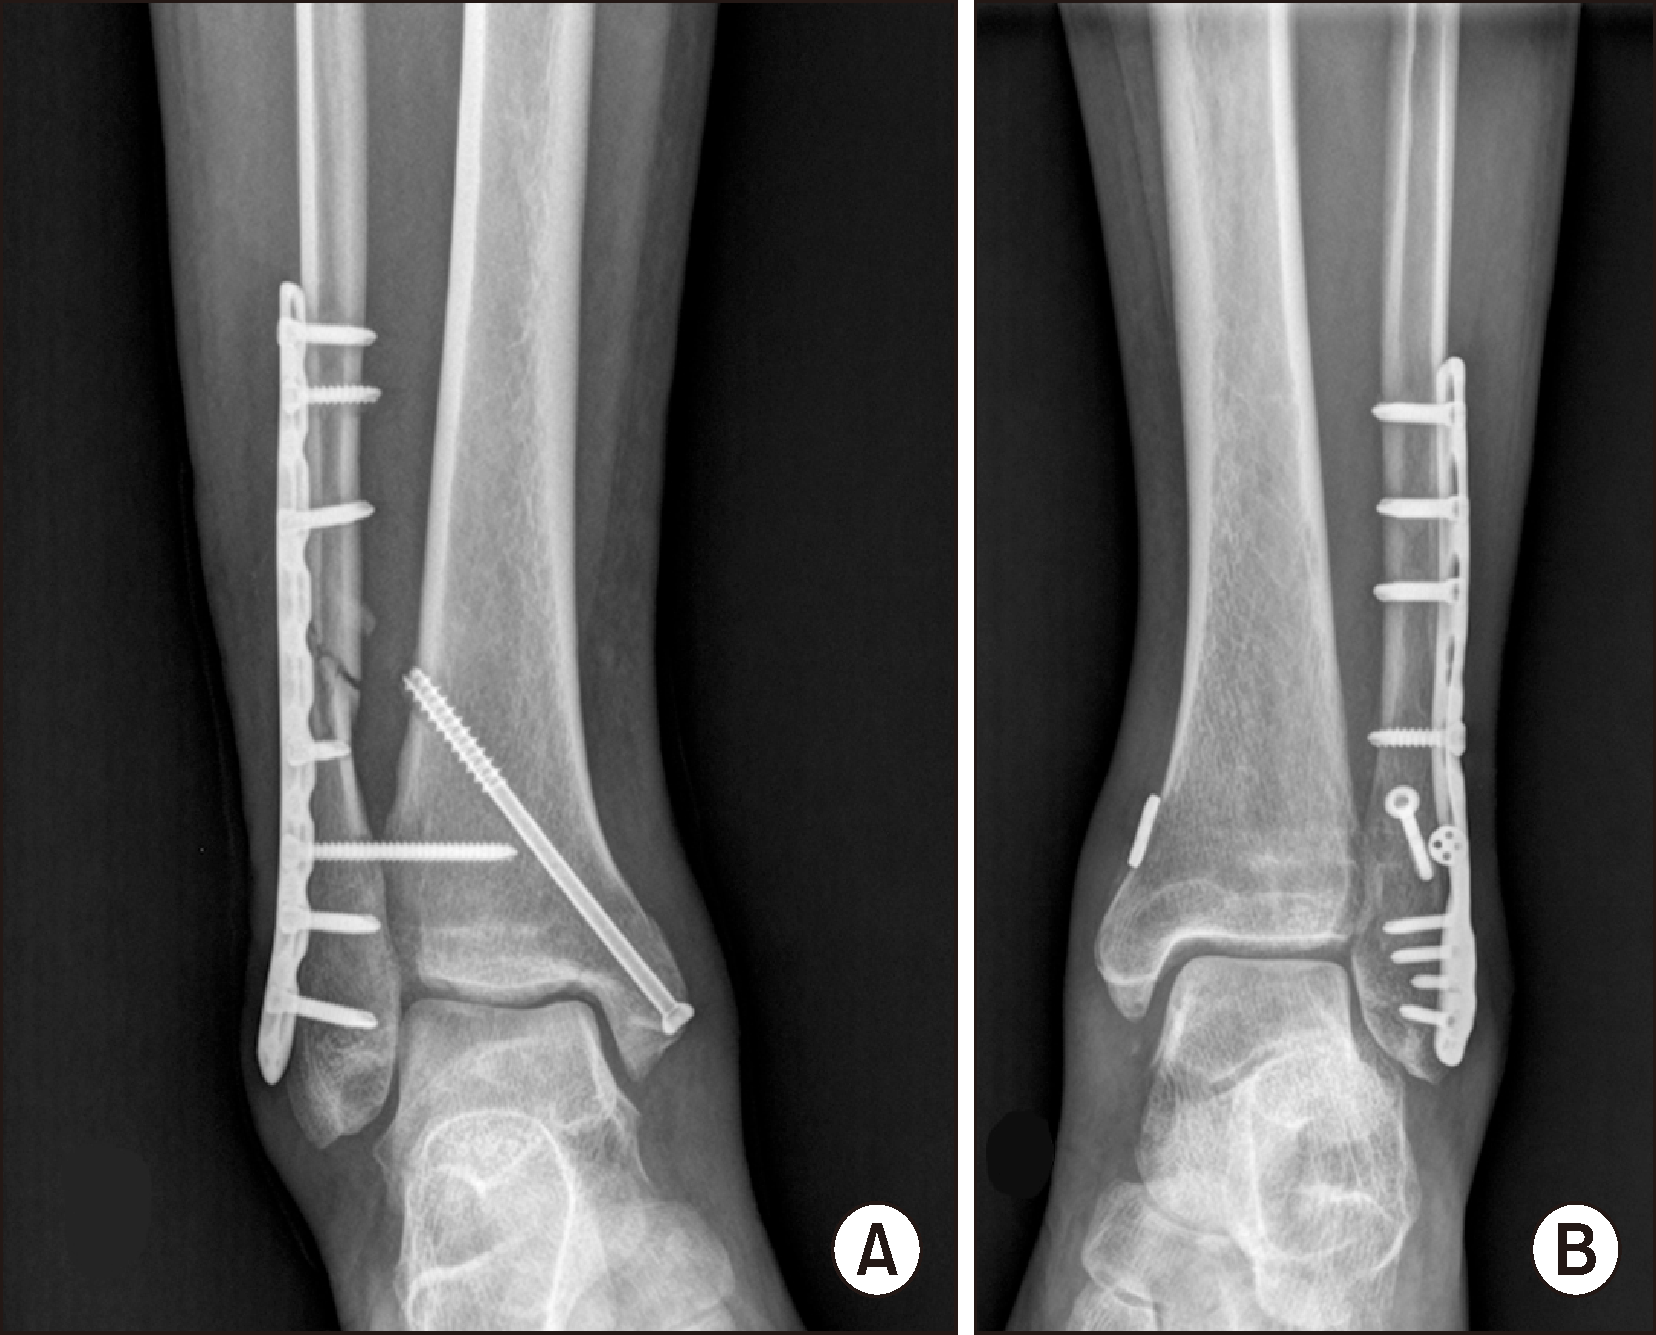

방사선학적 결과상 경비 간격, 경비 겹침, 내측 빈 공간의 측정치는 수술 전, 수술 직후 나사못 고정군과 봉합사 단추 고정군간에 통계학적으로 의미있는 차이가 없었으나 술 후 1년에서는 두 군간에 통계학적으로 의미있는 차이가 있었다(Table 4). 나사못 고정군과 봉합사 단추 고정군에서 수술 전과 수술 후 1년에 측정된 지표는 대응표본 t-test상 유의미한 정복 정도를 보여 나사못 고정 수술이나 봉합사 단추 고정 모두 효과적인 치료인 것으로 나타났다(Table 5). 나사못 고정군과 봉합사 단추 고정군의 수술 직후와 수술 후 1년의 측정된 지표에 대하여 대응표본 t-test를 하였는데 나사못 고정군은 의미있는 차이를 보여 수술 직후 정복된 정도가 1년이 지나자 다소 정복이 느슨해지는 것으로 나타났으며(Fig. 3), 봉합사 단추 고정군은 그 차이가 없어 수술 직후의 정복이 수술 후 1년이 지나도 잘 유지되는 것으로 판단되었다(Table 6).

나사못 고정술을 시행한 환자군 전례에서 평균 109.0일 이후에 나사못 제거술을 시행하였다. 나사못 고정술을 시행한 환자군에서 2명의 환자에서 나사못 부러짐이 발생하였다(Fig. 4). 나사못 고정군의 1명의 환자에서 상처 감염이 있었으며 상처 소독과 경구 항생제 복용을 통하여 치료되었다.

경비 결합 나사못을 이용한 고정술과 봉합사 단추를 이용한 고정술을 시행한 환자에서 방사선학적 지표에 대한 연구들은 여러 논문에서 다루어졌다. Laflamme 등7)은 동적 고정이 정적 고정보다 더 나은 방사선학적 결과를 보인다 하였다. Zhang 등5)은 봉합사 단추로 수술한 경우 부정 정복의 위험이 덜하다고 하였다. 본 연구에서는 경비인대 나사못을 이용한 환자군과 봉합사 단추를 이용한 환자군에서 수술 직후 방사선적 지표는 차이가 없었으나 수술 1년 후 방사선학적 지표를 비교하였을 때 봉합사 단추로 치료한 환자군이 수술 직후의 관절 정복된 정도를 수술 1년까지도 변함없이 유지하는 것으로 나타났다. 나사못 고정으로 치료한 환자군은 수술 직후에 얻었던 정복이 수술 1년이 지난 뒤에는 다소 느슨해 지는 것으로 확인되었다. Schepers 등16)은 나사못 제거 후에 6.6%에서 원위경비관절의 재이개가 발생하였음을 보고하면서 나사못을 조기에 제거하는 경우 재이개의 발생이 높아지니 최소 수술 후 8∼12주 후에 제거할 것을 권하였다. 그러나 본 연구에서는 전례에서 12주 이상이 지나서 나사못을 제거하였는데 재이개까지는 아니었지만 원위경비관절이 다소 벌어지는 것으로 나타났다. 이렇게 다소 느슨해지는 현상이 어떤 결과를 초래할지에 대해서는 장기적인 추시가 필요한 부분이나 술 후 1년이 지난 시점에서 AOFAS 점수로 평가한 임상적인 결과는 봉합사 단추 고정군과 차이는 없었다. Jordan 등17)과 Hosin 등18)도 나사못 제거 후 원위경비관절이 벌어지는 것을 보고하였다. 그러나 경미하게 벌어지는 것이 임상 결과에는 영향이 없음을 보고하였는데 본 연구의 결과와 유사한 소견이다. 12주가 인대가 하중을 견딜만큼 견고한 치유를 얻기에 부족한 기간인지 아니면 체중부하를 허락하지 않는 치료법이 인대의 재형성에 좋지 않은 영향을 미치는 것인지는 명확한 판단이 힘들 것으로 보인다.